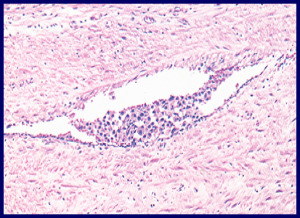

Nach Entfernung des tumortragenden Hodens wird dieser entsprechend der Empfehlungen der WHO genauestens mikroskopisch analysiert, um alle feingeweblichen Subtypen der testikulären Keimzelltumoren identifizieren zu können. Ebenso muss das Vorliegen einer vaskulären Invasion (Abbildung 4) beschrieben oder definitiv ausgeschlossen werden. Diese Informationen sind für die spätere Therapieplanung wichtig, da beispielsweise ein hoher Anteil an embryonalem Karzinom in Kombination mit einer vaskulären Invasion im klinischen Stadium I eines nichtseminomatösen KZT (siehe unten) mit einer hohen Rate mikroskopischer Lymphknotenmetastasen assoziiert ist und die Option einer adjuvanten Therapie eröffnet.